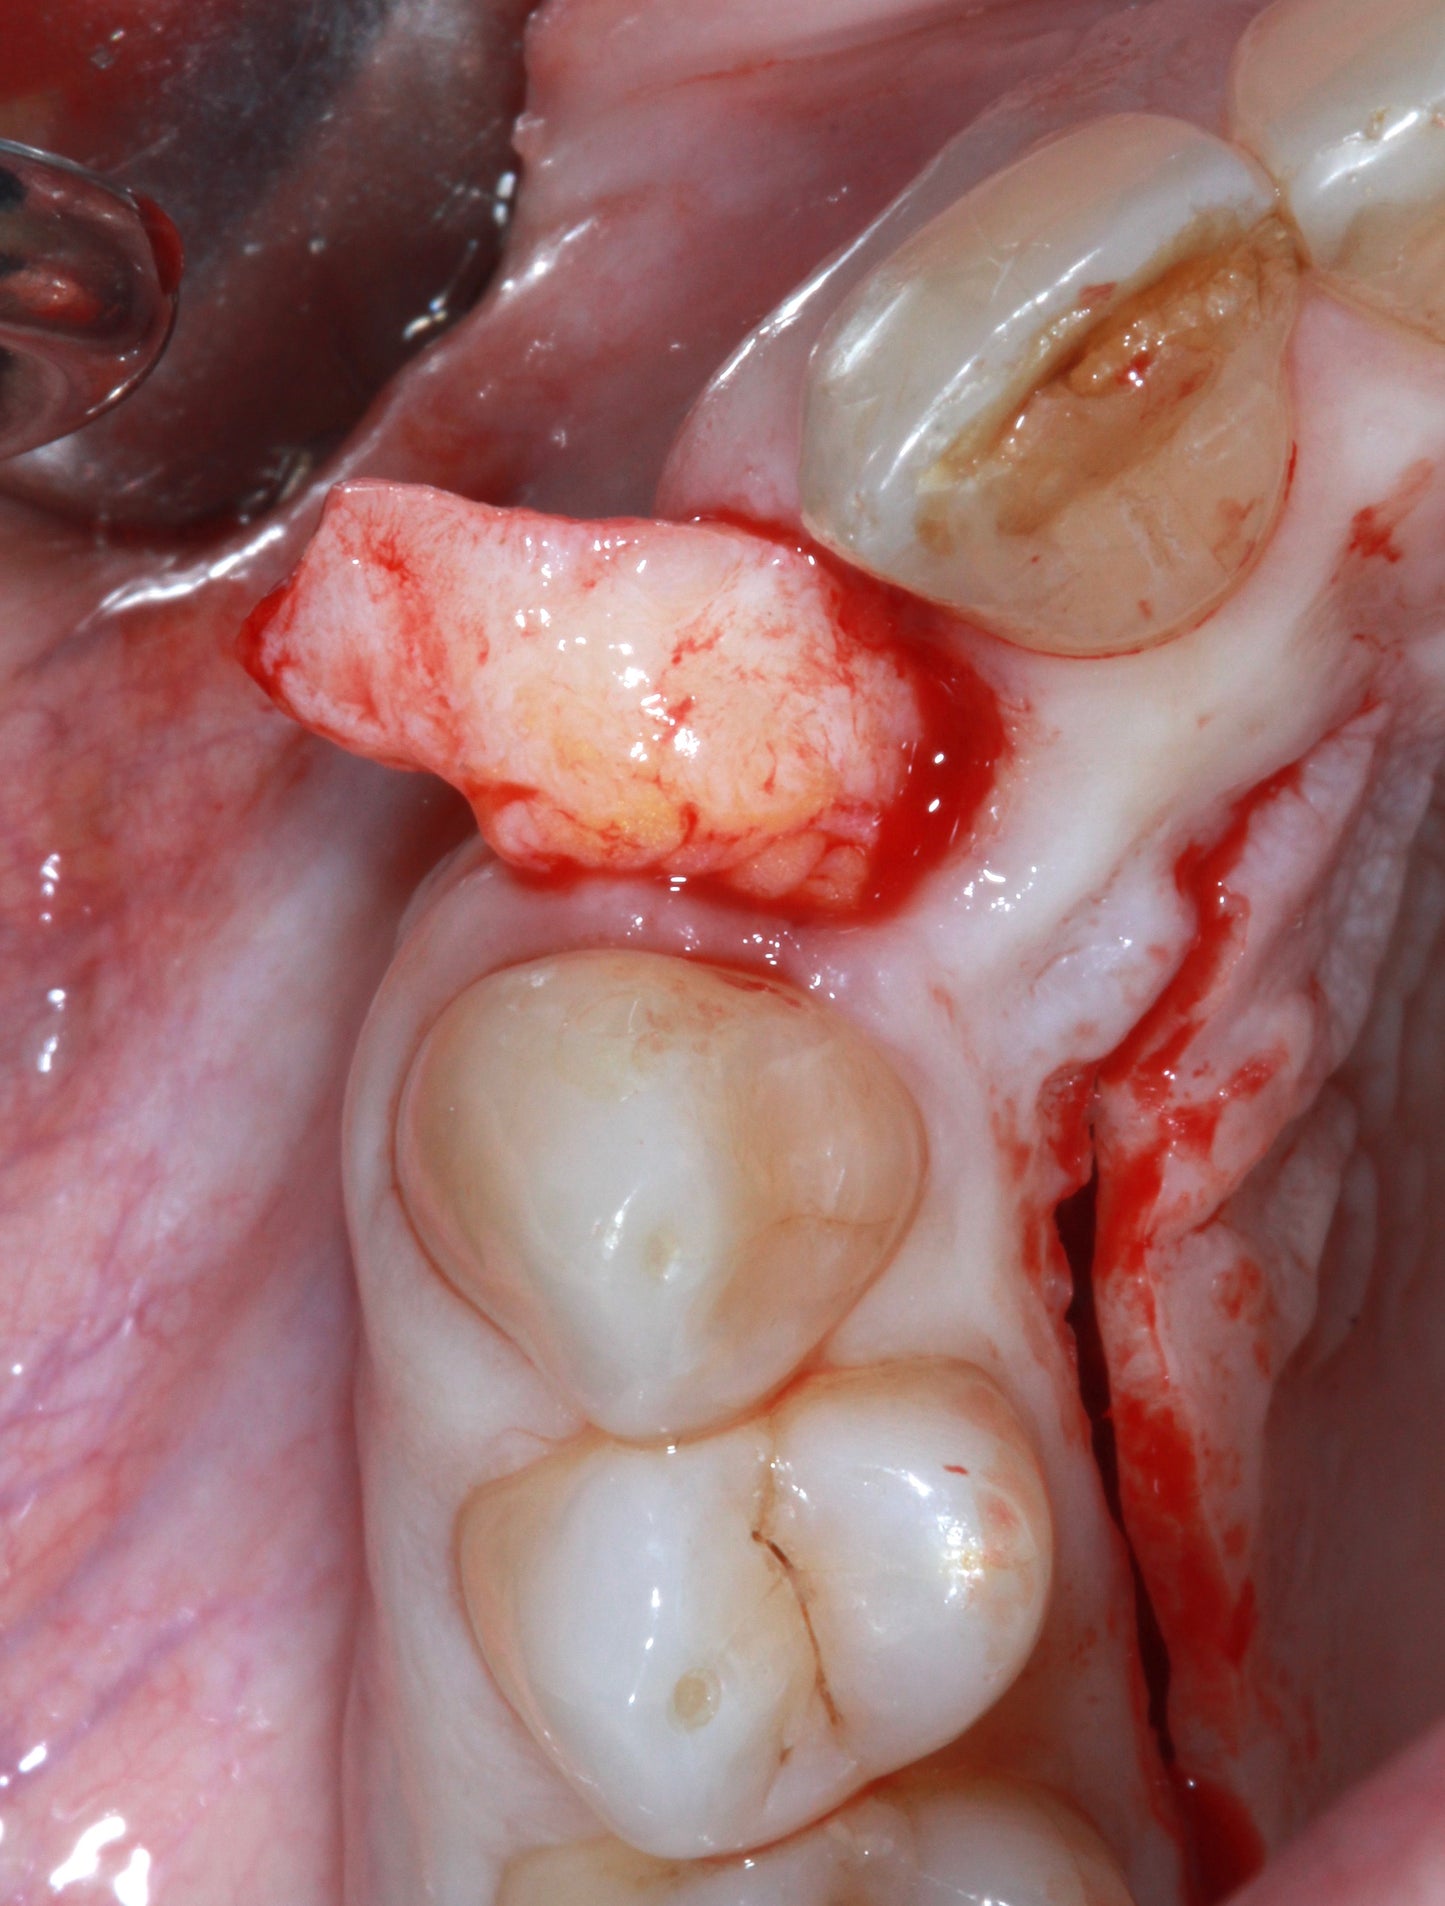

Harvesting techniques: Free gingival graft, Connective tissue graft, Tuberosity harvest, Retromolar and edentulous ridge harvest

Step by step techniques: Apically positioned flap, Vestibuloplasty, Lingually positioned flap, Rotated palatal pedicle, Roll flap and modifications, VISTA/tunnel techniques, Vertical volume augmentation

Harvest of autogenous tissue

Socket grafting with palatal pedicle